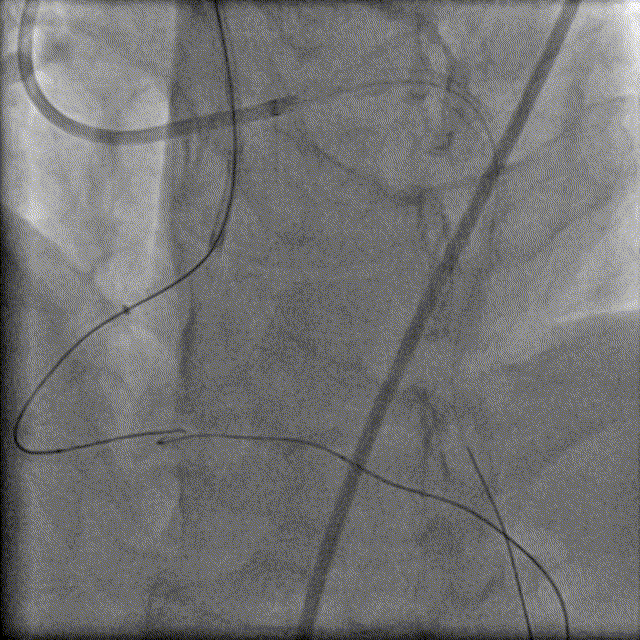

换用Instantpass微导管(170cm)支撑下送Fielder XT-R导丝通过LAD-RCA心外膜侧枝逆向通过RCA闭塞病变,推送微导管后交换Gaia Third导丝,RCA正向送Telescope™导引延长导管进行主动迎接Gaia Third导丝。

1.5×15mm、2.0×15mm、2.0×20mm、2.0×15mm Emerge球囊以10atm×15秒扩张PLA及RCA病变。

于PDA-RCA开口近段病变处植入2.5×30mm、2.75×30mm、3.0×30mm、3.5×22mm Resolute Integrity支架,2.0×15mm Emerge球囊主动拘禁保护PLA。

3.0×15mm、3.5×15mm NC Sprinter球囊以12-16atm×15秒后扩。